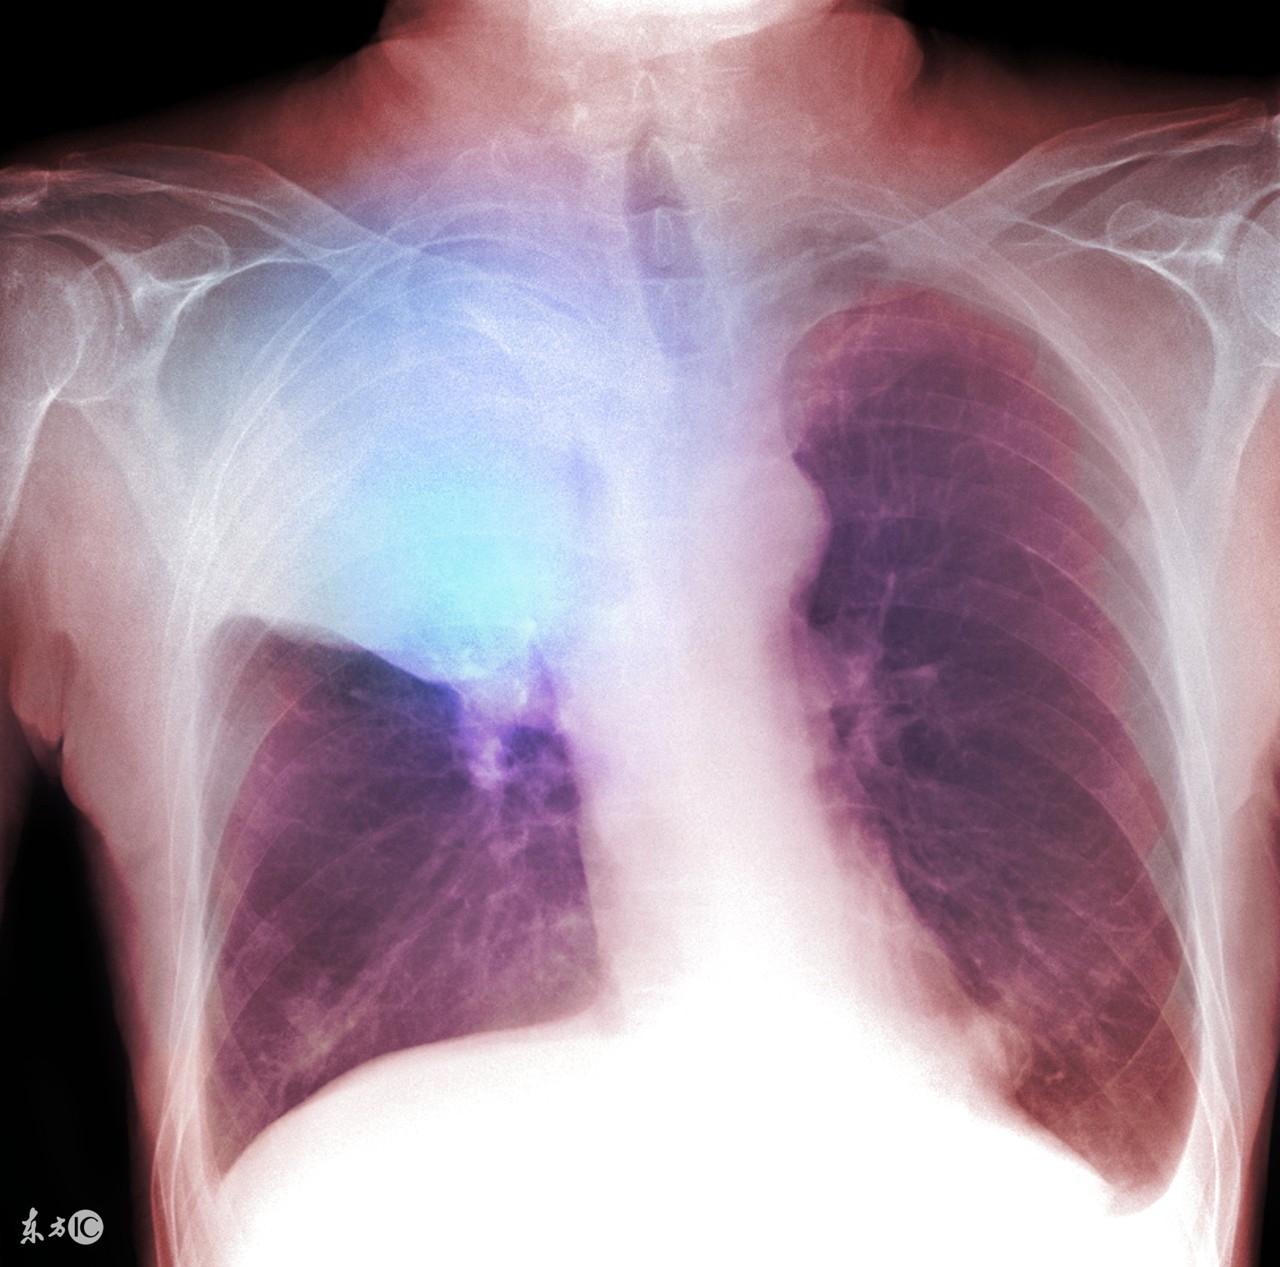

肺假性肿瘤可以通过X线检查、CT检查、纤维支气管镜三种方式检查出,所以并不难诊断。因此诊断出肺假性肿瘤的几率越来越高,对患者查明病情、对症治疗、消除患者顾虑有很大的帮助